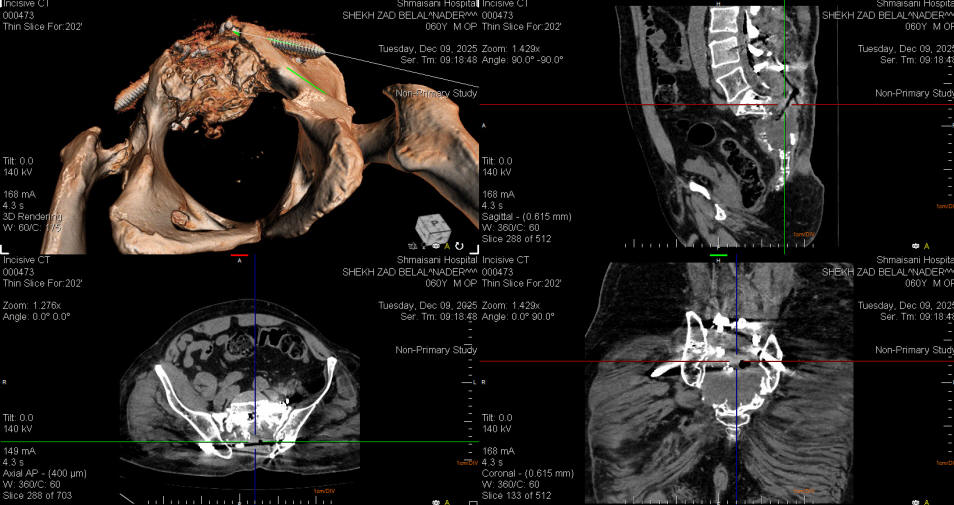

10-DEECEMBER-2025  SHIRZAD BELAL NADER  60 YEARS  REVISION OF THE ILIAC SCREWS AND REDIRECTION.

The patient was operated by me 08-December-2025 for progressing chordoma. The patient neurological status improved, but check CT-scan of the pelvis done the next day with ORS Visual program showed unacceptable direction of the iliac screws, for what he was brought to the operating room to redirect the iliac screws.

The wound was opened and further dissection lateral to sacroiliac joint was accomplished to visually follow the track of the screw to be kept inside the bone. Calculation of the direction of the iliac screws according to ORS Visual software was to put the screws 20 degrees more medial in the saggital plane. The right iliac screw was 70x9.5 mm and to the left 60x9.5 mm in dimensions. Visual control denied any violation of the iliac bone. Inspection of the tumor cavity was filled by hematoma which was removed and the neural structures were swollen. Routine closure of the wound. Smooth postoperative recovery. He was sent to the ward.

The iliac screws were redirected more lateral and violate the gluteal muscles. Redirection was mandatory to achieve prompt fixation.

This error was caused by abnormal pelvic cavity with the anaplasia of the left femoral head and absence of the iliopsoas muscle in the left side with thin bone in the left side.

Check CT-scan performed 11-December-2025 with ORS Visual software showing the iliac screws inside the iliac bones.